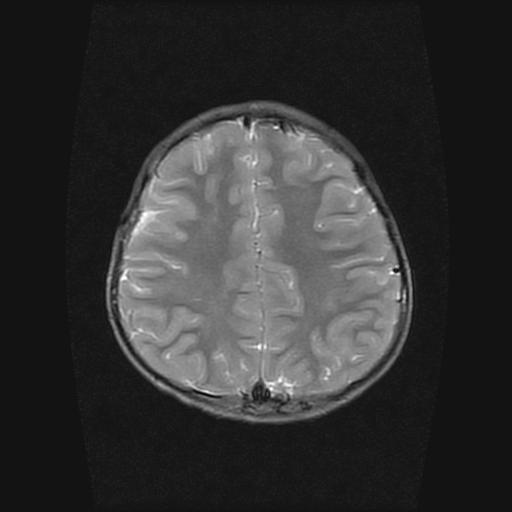

6岁小儿,左侧视神经瘤术后。现左侧视力减退。